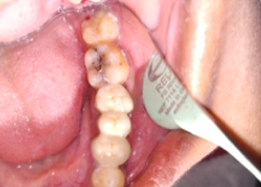

Hemisectomy

Post-OP Clinical View